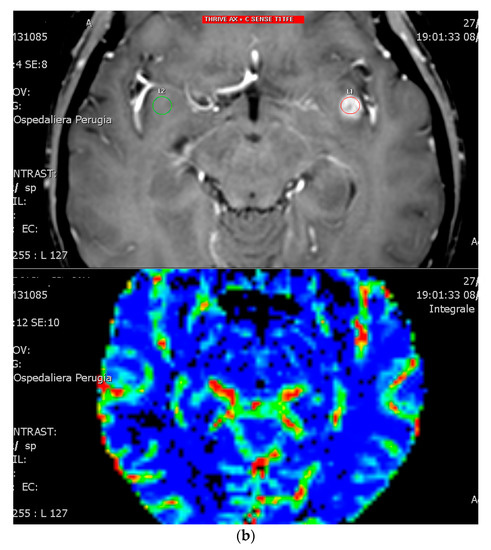

3.2. Diffusion and Perfusion MRI